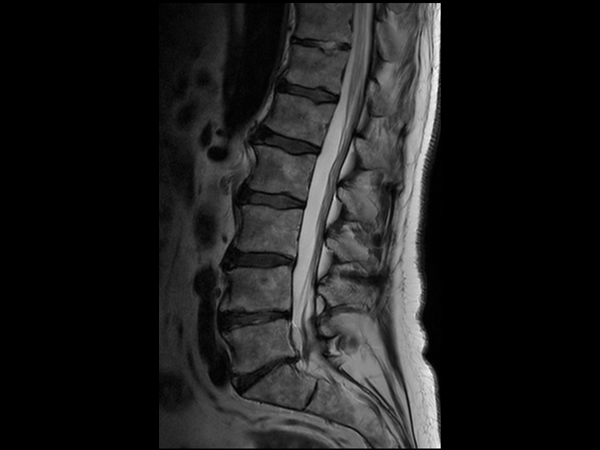

Comprehensive Lumbar Spine imaging at 3.0T